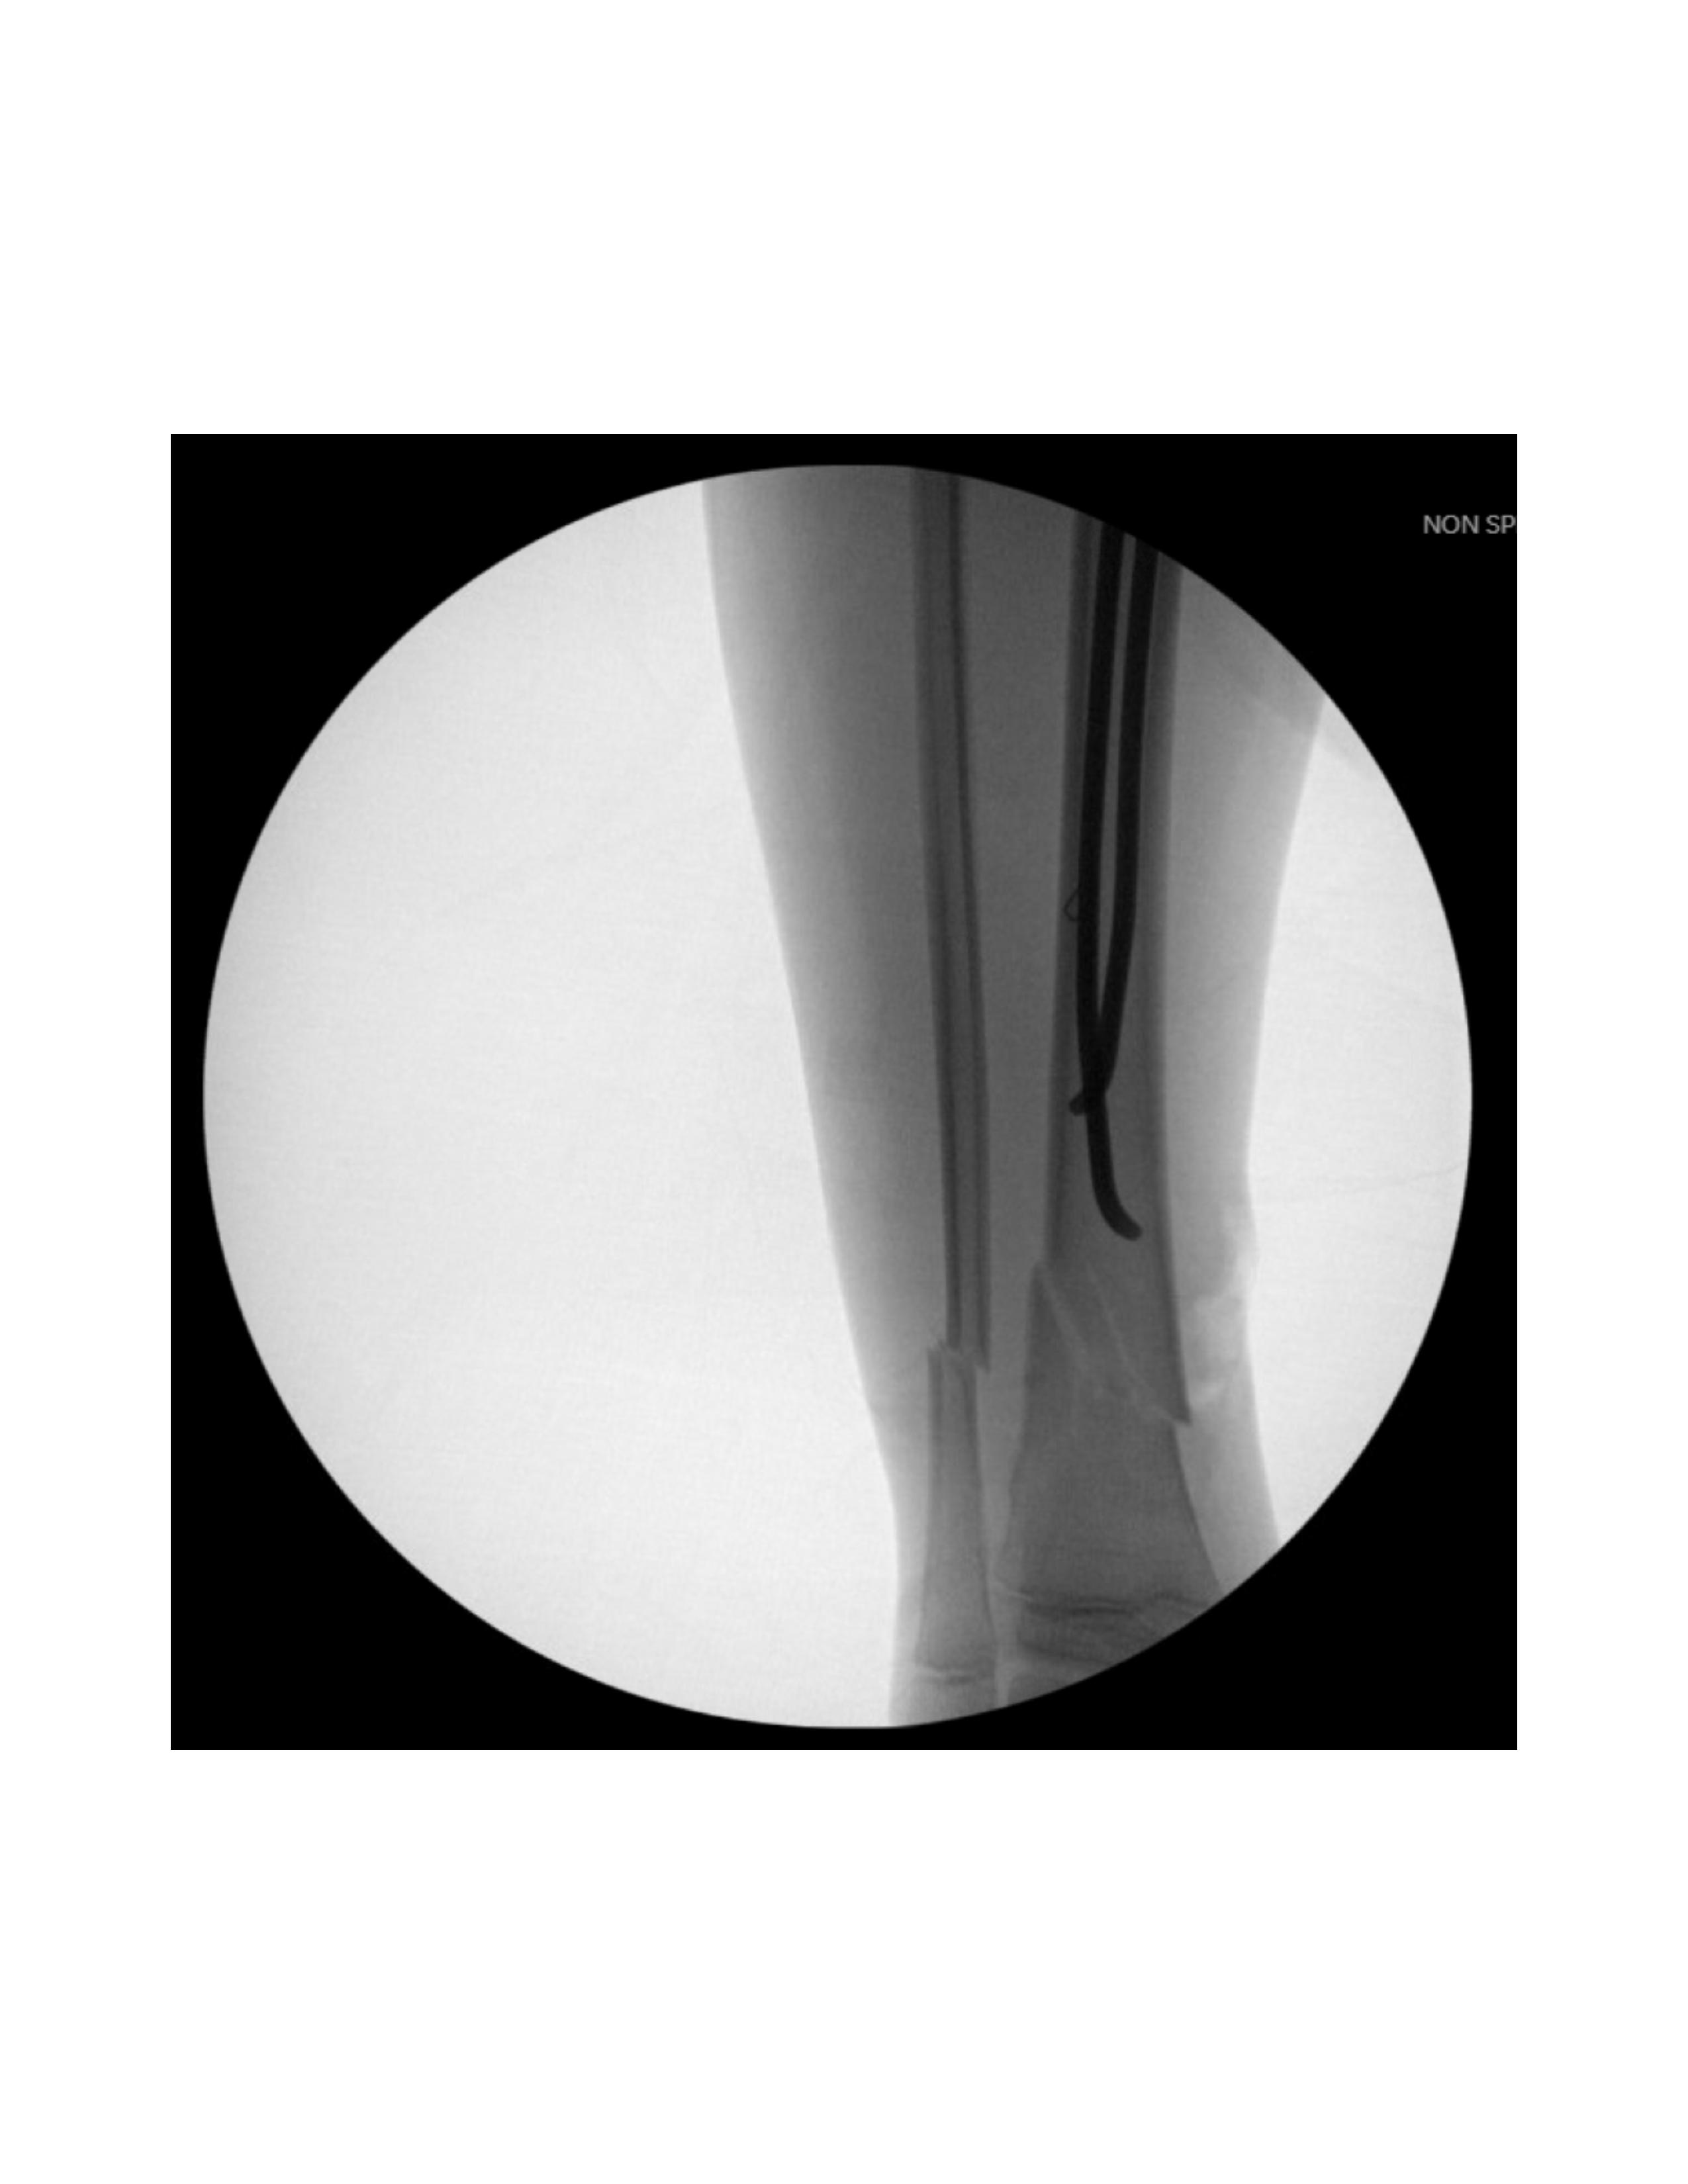

Next, nail selection involves choosing either titanium nails for flexibility and rotational stability, or stainless steel nails for added rigidity and children over 45 kg [6,7]. Each nail should be 0.4 times the medullary canal diameter. In children ages 6-8, 2.5 mm nails are recommended, 3 mm for ages 8-10, 3.5 mm for children older than 11, and 4 mm for skeletally immature adolescents. Nail length is determined as 20 mm from the distance between the proximal and distal tibial physis. Given the distal location of the fracture site, a curvature of up to 40° is applied to the distal end of the nail so the apex of the curve reaches the fracture site, aiding in reduction stabilization.

Next, lateral entry point is made with a 2-3 cm longitudinal incision over the anterior compartment musculature between the tibial crest and the fibula head, 10-30 mm distal to the proximal physis. After blunt dissection, fascia splitting anteriorly, and lifting the anterior 6 compartment musculature off the tibia, a drill is utilized under fluoroscopy to enter the cortex anterior to the lateral border of the interosseous membrane attachment site. The modified nail is inserted using an inserter/T-handle with the curved tip perpendicular to the medial cortex (Figure 3). Oscillatory motions facilitate entry into the medullary canal until contact is made with the far cortex. The nail is then advanced by a mallet proximal to the fracture site before addressing the medial nail.

Next, the fracture is manually reduced and both nails are gently advanced past the fracture site by mallet. The curvature of the nails and their tips assists in reducing and stabilizing the fracture, inserted shy of the growth plate. Nail positioning is confirmed by fluoroscopy (Figure 5).